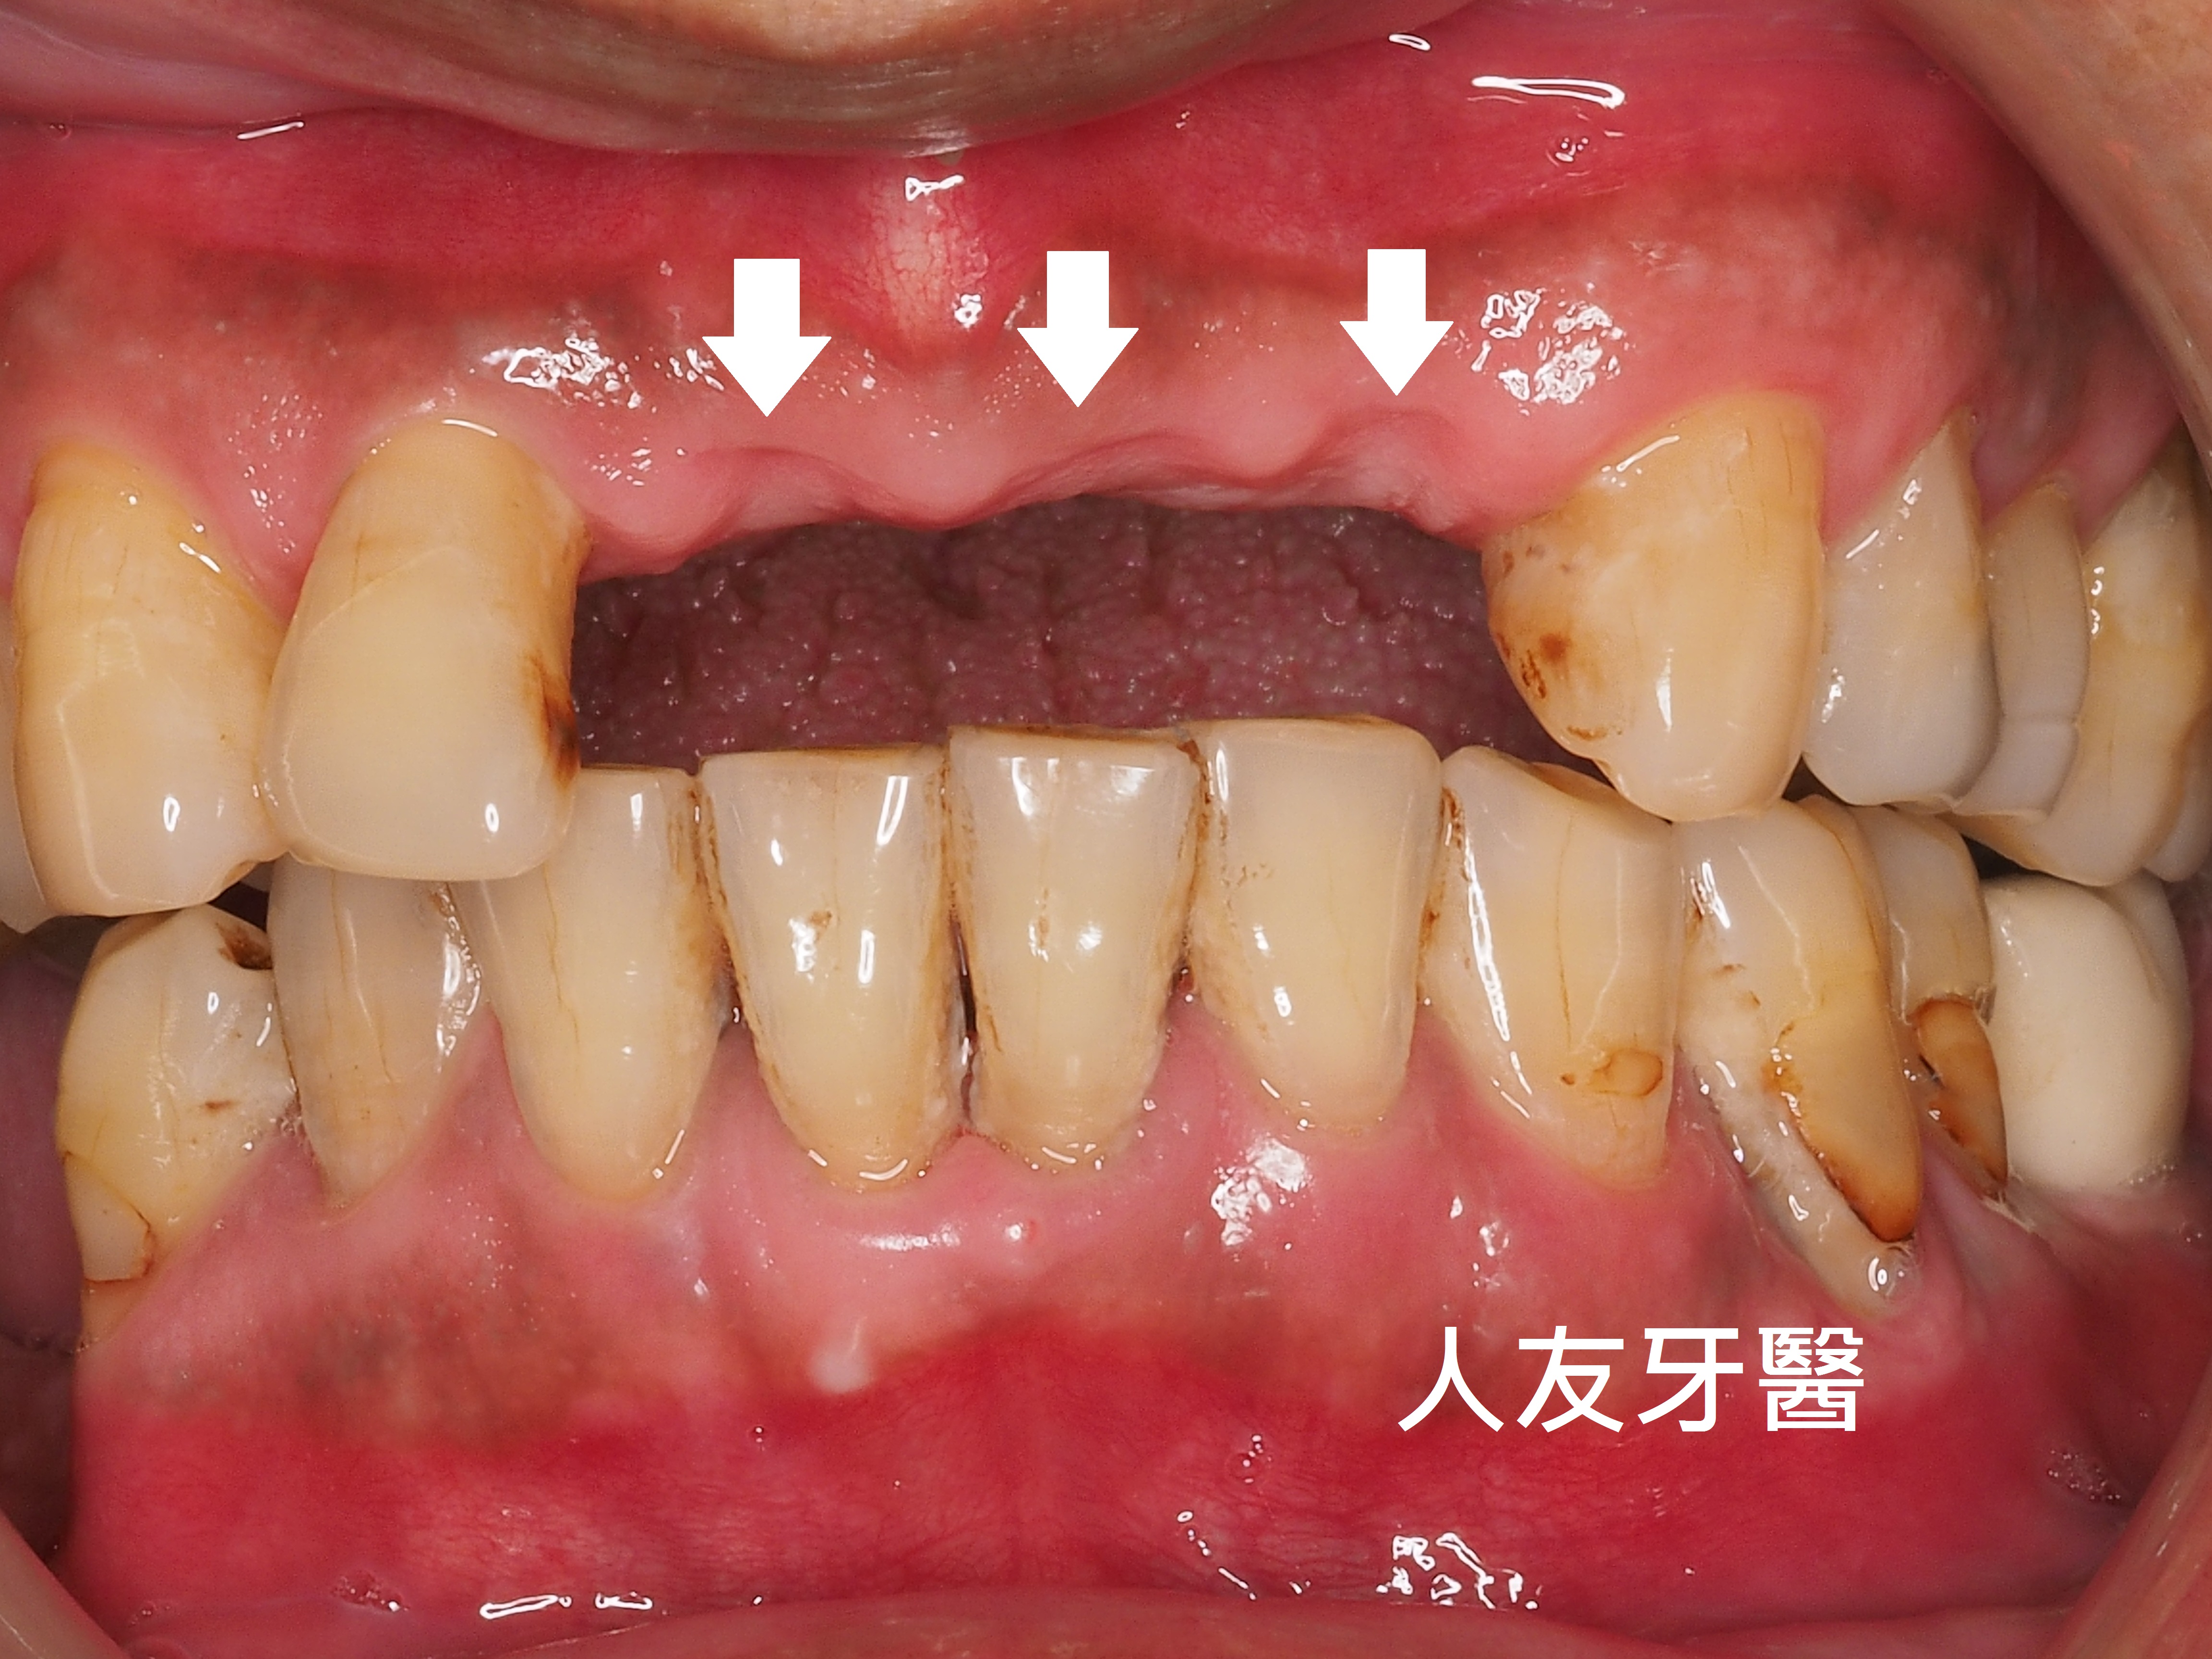

虎牙(犬齒)暴牙缺點(上左右2圖):

口腔清潔困難:虎牙暴牙形成清潔死角,易積聚牙菌斑和牙結石,增加蛀牙、牙周病風險。

影響咀嚼與咬合:犬齒主要功能是撕裂食物,位置不對會影響咬合功能,使食物難以充分咀嚼。

發音問題:虎牙暴牙可能影響舌頭的靈活性,導致發音不清晰。

口腔黏膜受傷:也可能經常摩擦或咬到嘴唇、臉頰內側,造成破皮或不適。

形成口呼吸:嘴巴不易閉合,容易養成口呼吸習慣,導致口臭、臉部肌肉鬆弛等問題。